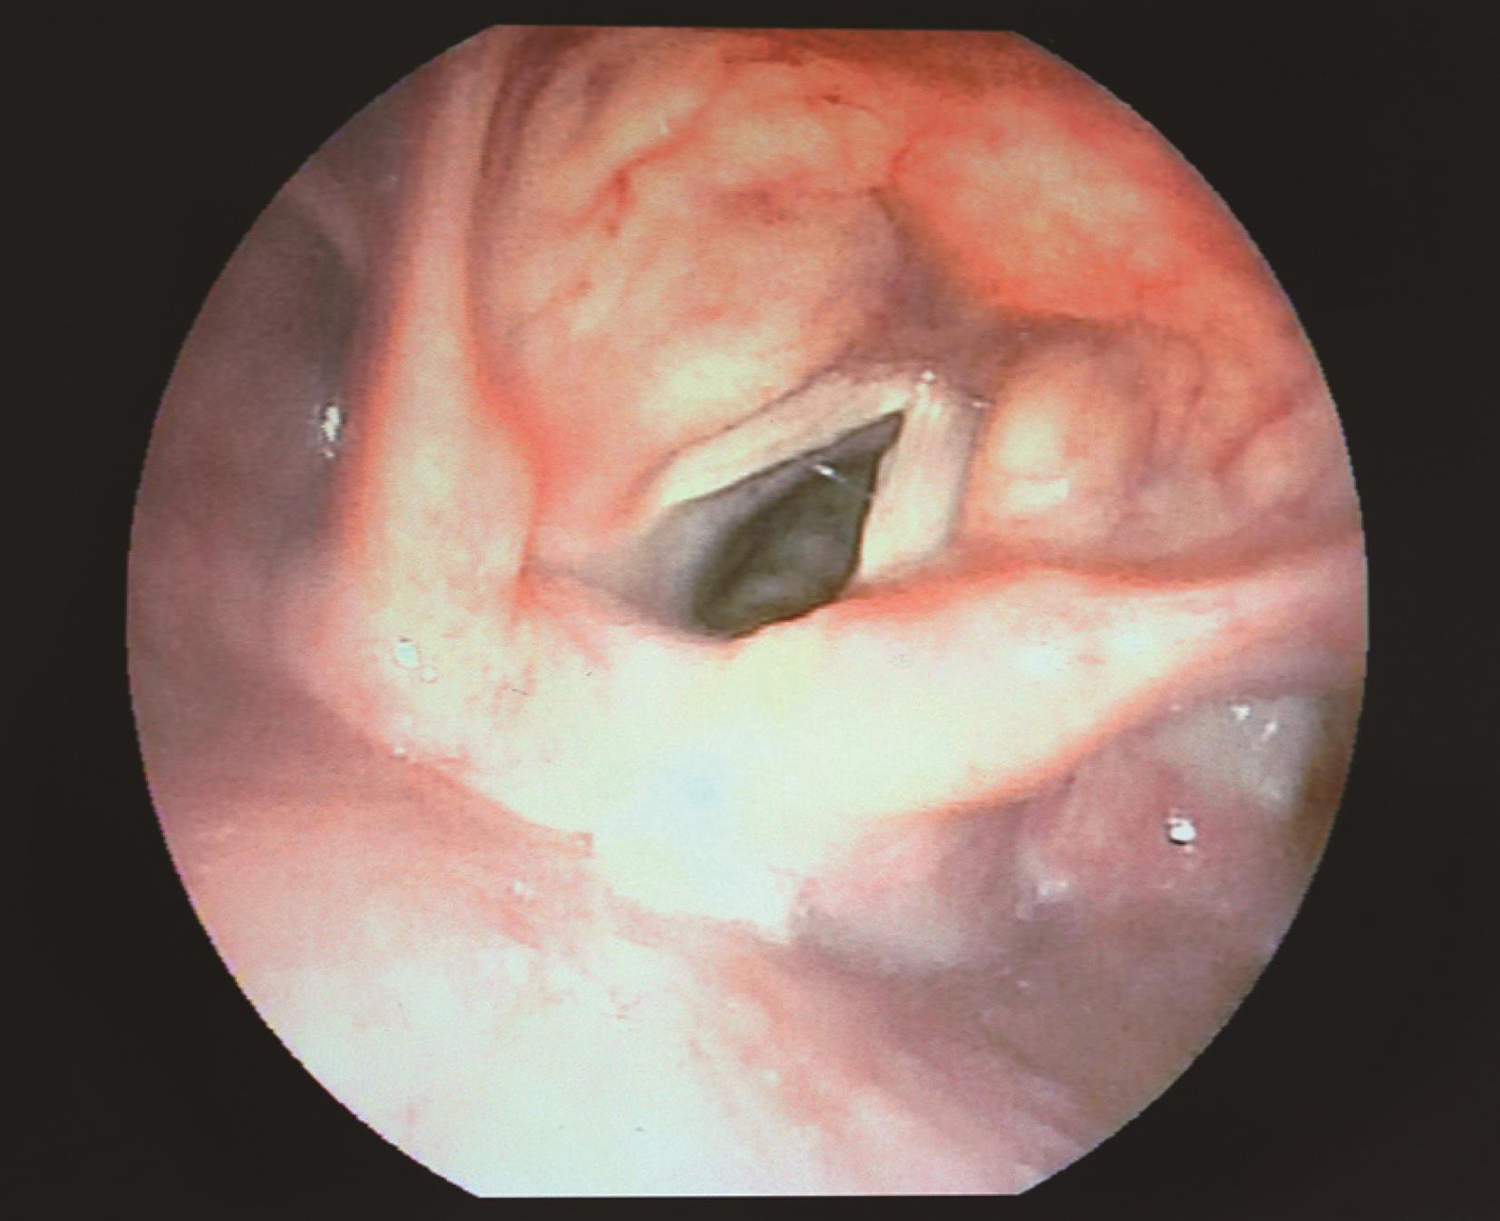

3.2017年8月10日电子喉镜

右侧声带固定于旁正中位,闭合时有裂隙(图5,图6)。

图5 喉镜示右侧声带固定于旁正中位

图6 喉镜示声带闭合时裂隙